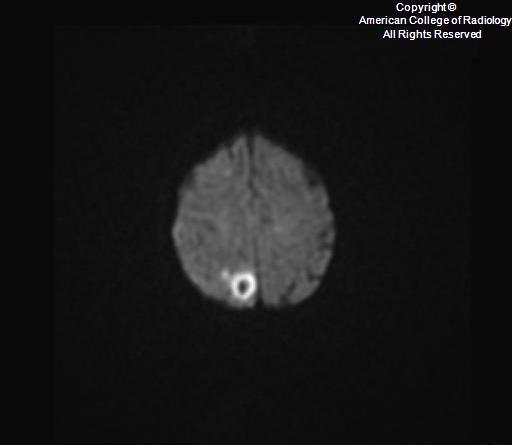

DDx of restricted diffusion on brain MR

A

• ischemia

• abscess

Configuration of cerebral lesiosn that demosntrate restricted diffusio

• rounded, diffuse restriction –> infectious etiology - abscess or septic emboli

• restriction only in the walls and projections of the lesion (not in its core)–> fungal abscesses

• special with fungal (esp with aspergillosis infection/abscess): T2-hypointense zones and magnetic susceptibility within the wall of cerebral Aspergillus lesions can be attributed to a dense population of Aspergillus paramagnetic hyphal elements, especially iron and magnesium, which are essential for hyphal growth. It has also been postulated that this MR finding may correspond to hemorrhage in the capsular wall.